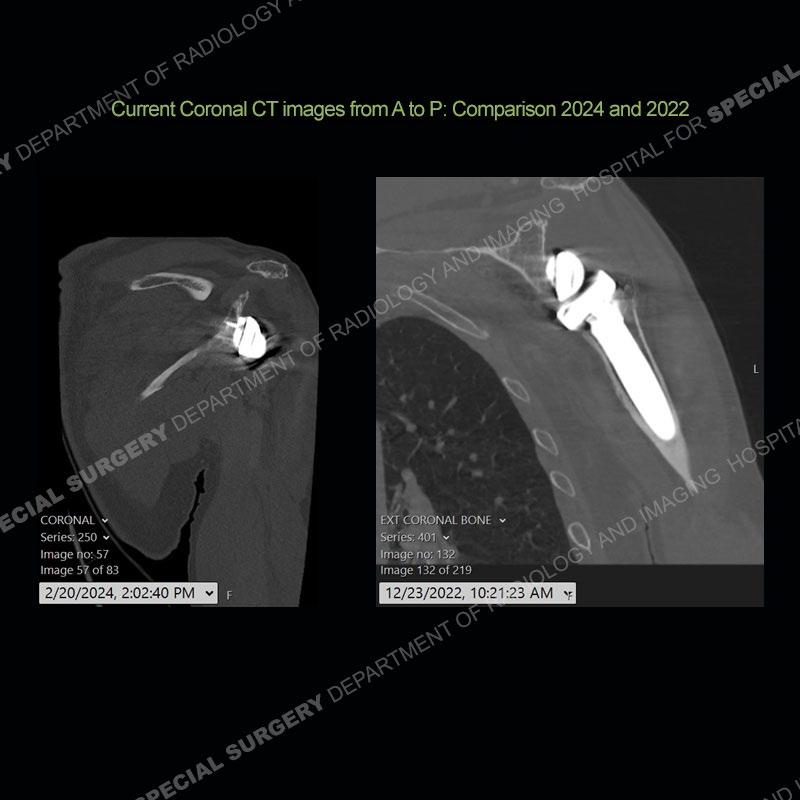

When comparing the radiographs, there is a slight change in the alignment in the components of the prosthesis. On the current radiographs, a radiolucent, crescentic focus is present at the level of the glenoid. When comparing the CT exams, there is a change at the alignment of the glenosphere and the humeral component and now a direct apposition of the components. On the current CT, the radiolucent, crescentic focus is again identified.

If comparison radiographs are present, subtle changes can be made more apparent. Instead of a space between the glenosphere and the humeral tray, there is a direct contact, and there may be an overall change in the alignment at the articulation. The displaced, radiolucent polyethylene liner depending on location can be seen on the radiographs, as in this case. At times, the liner may overlie other structures making identification very difficult on radiographs, but it should almost always be able to be identified on CT (as shown in this example as well). This patient is scheduled for revision procedure.